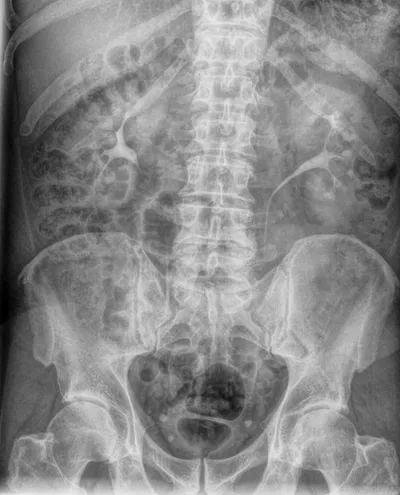

L'urographie intraveineuse (UIV) est une technique d'examen radiologique qui permet d'explorer la morphologie du rein et la fonction rénale.

Ses indications incluent : obstruction des voies excrétrices, recherche de calculs, de tumeurs ou de métastases, reins ectopiques, uretère ectopique et hydronéphrose.

Préparation : le patient doit être à jeun depuis 4 heures. Une injection intraveineuse d'une solution iodée est réalisée, puis l'urographie est effectuée immédiatement après l'injection.